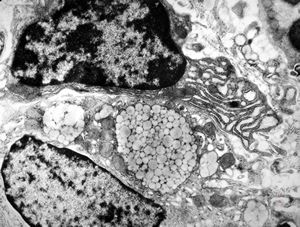

M,29y. | jejunum - lipid malabsorption

jejunum … lipid malabsorption

Whipple disease - lipid malabsorption